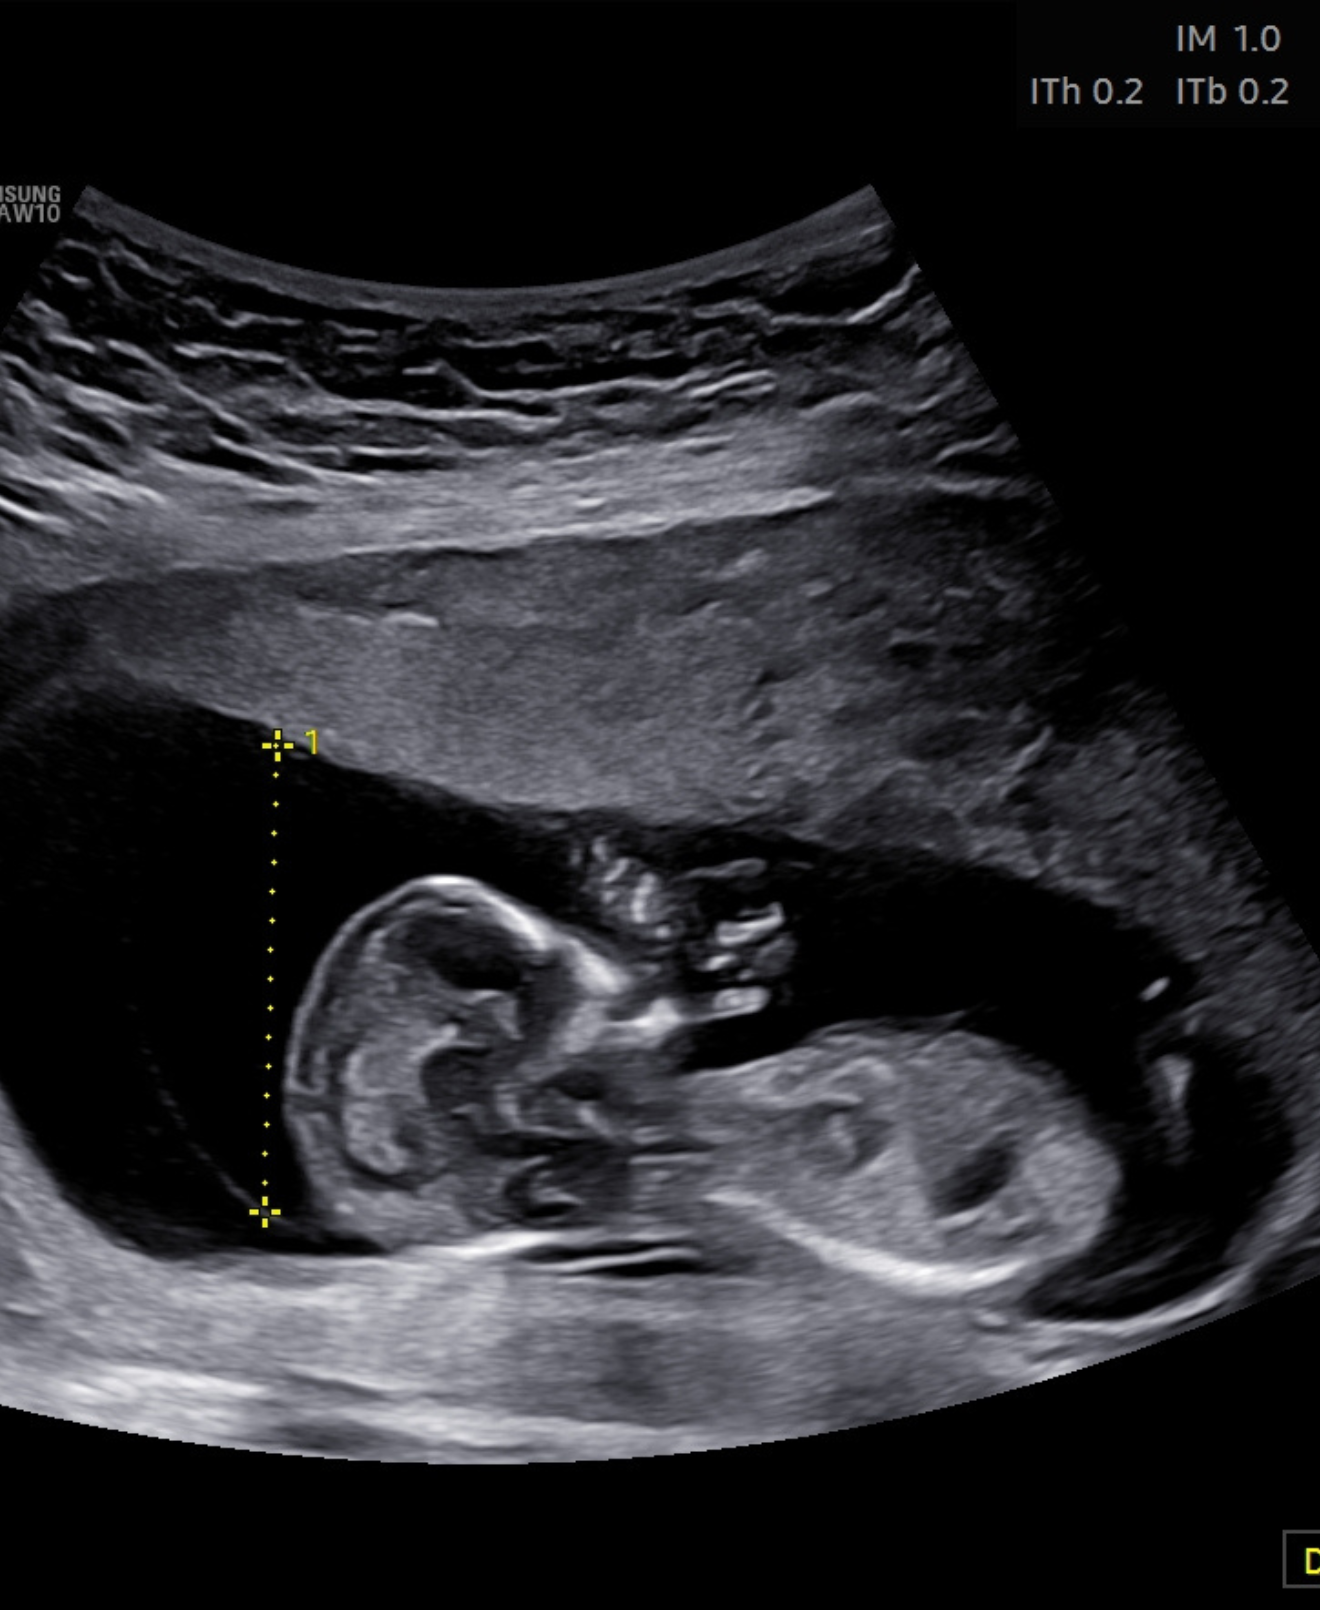

Ecografía de Detalle Anatómico

Perfil Biofísico